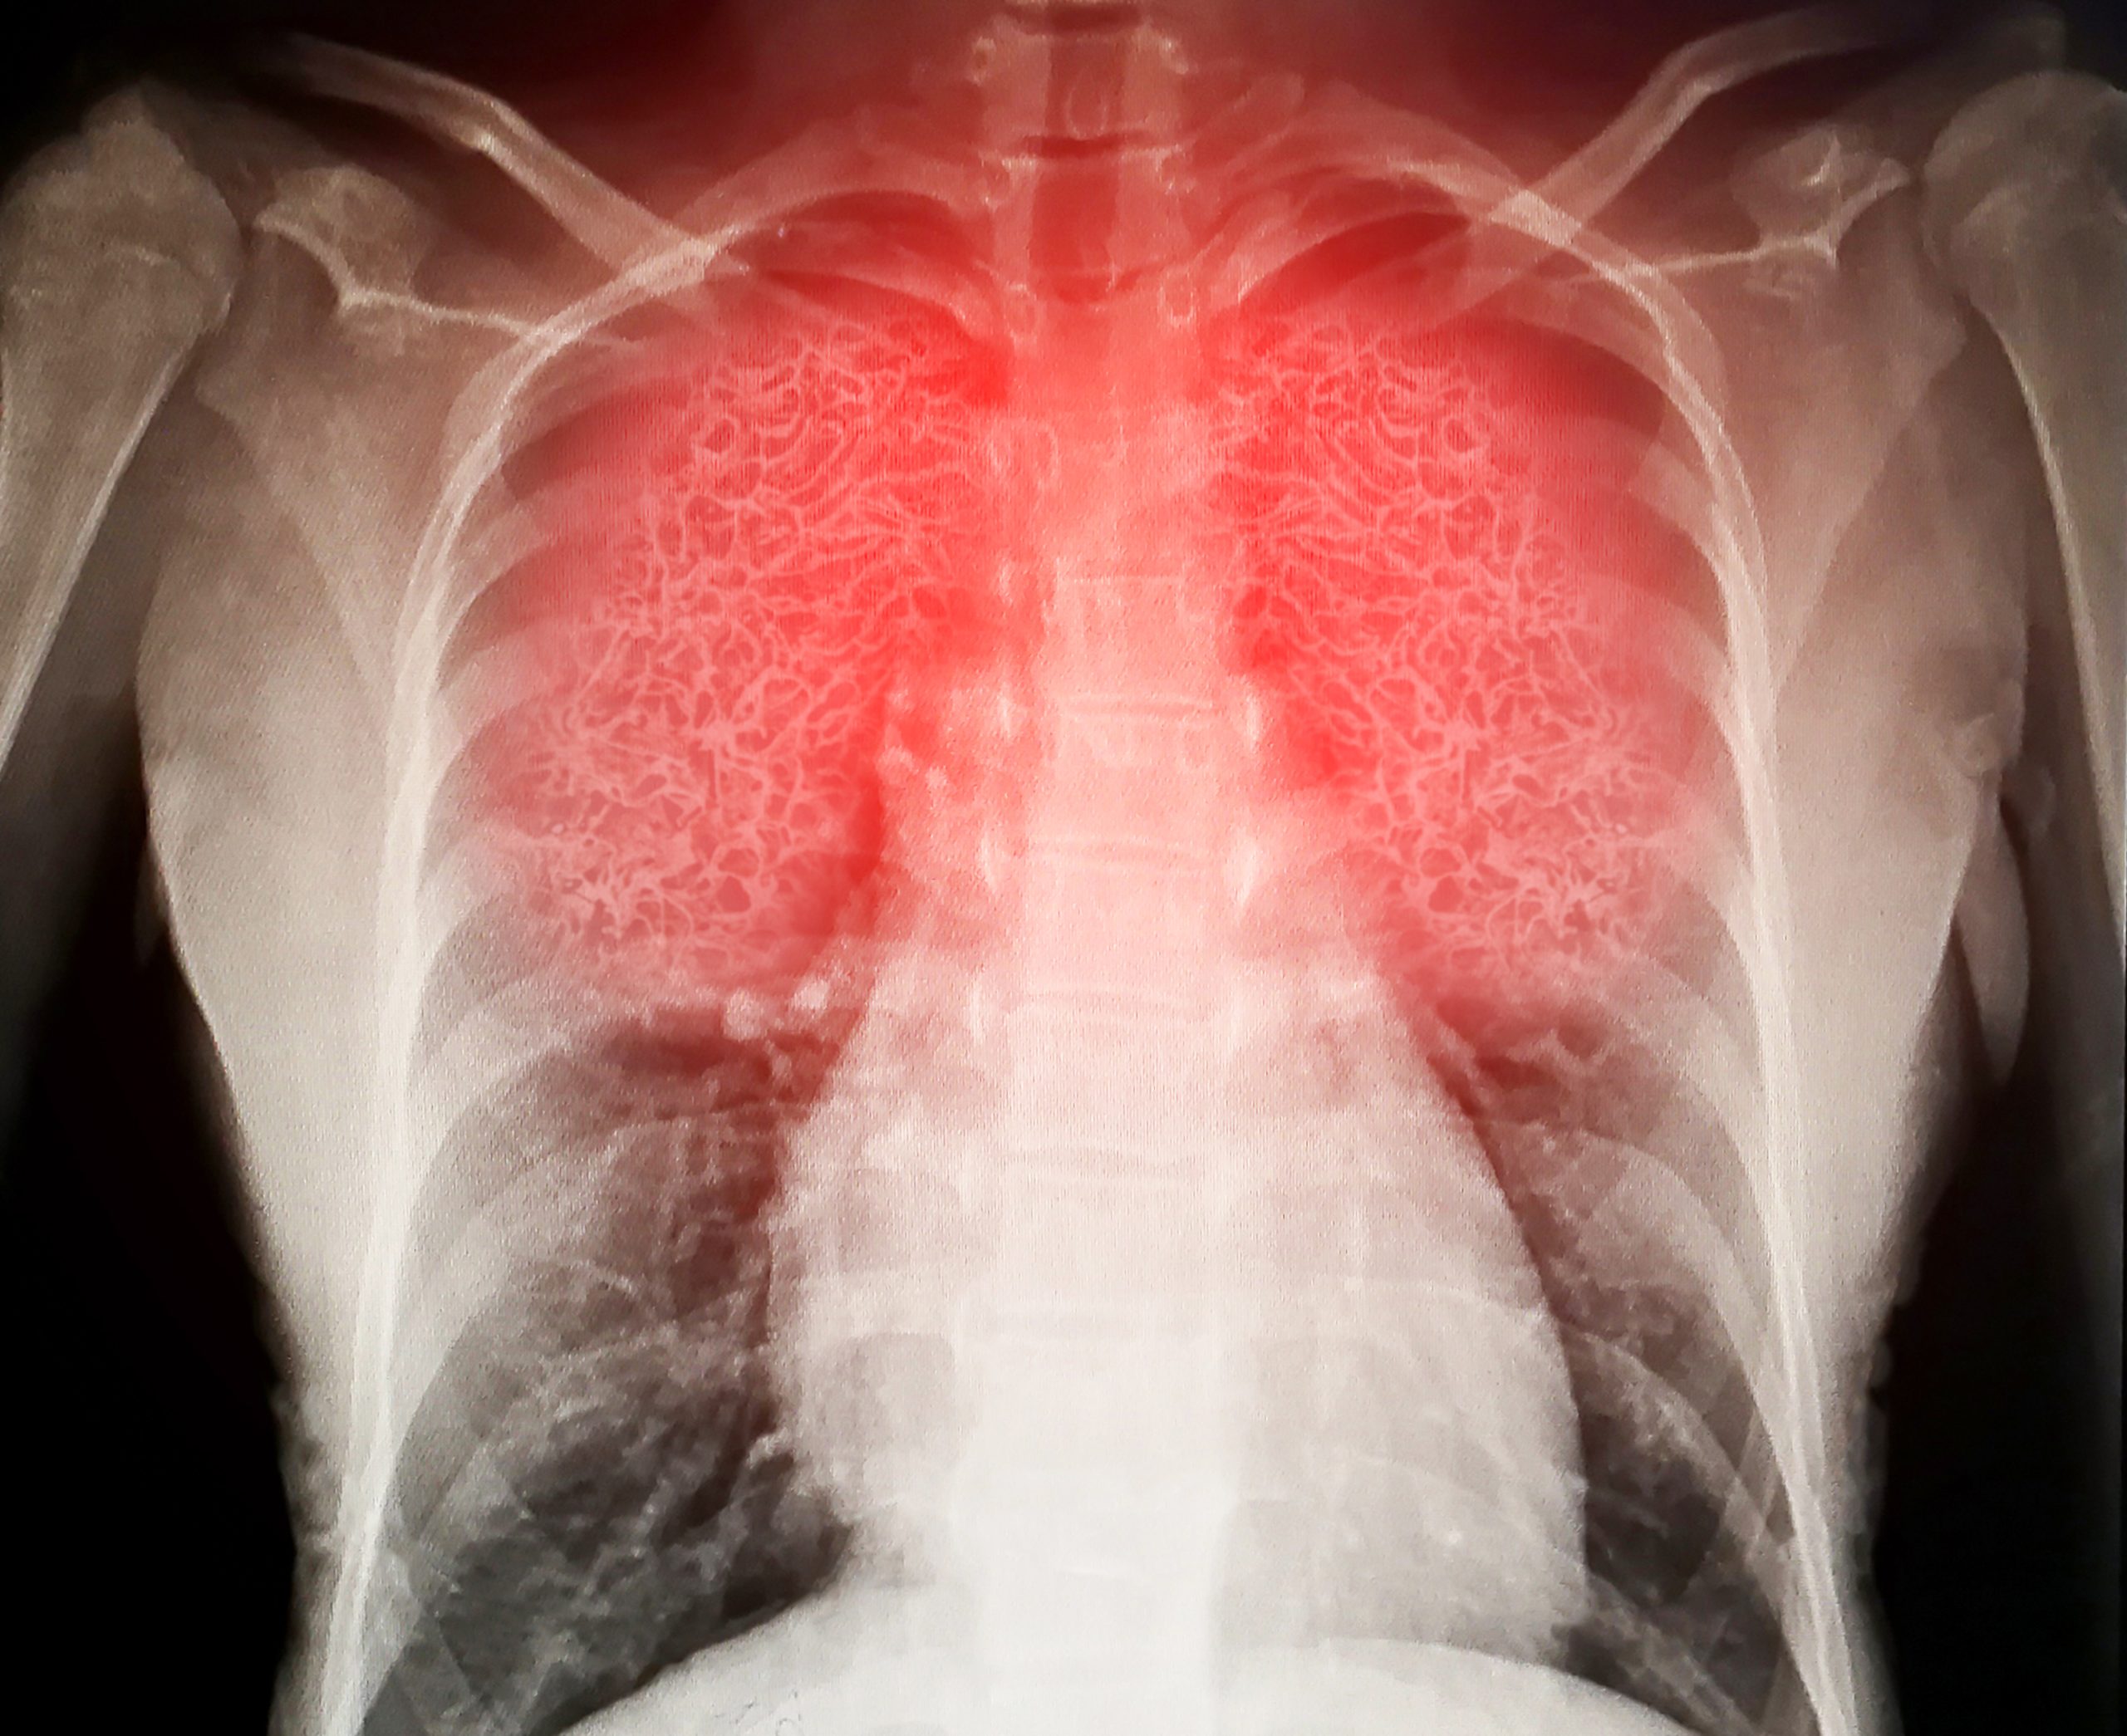

Las enfermedades respiratorias, en especial la neumonía, se han convertido en la principal causa de atención médica en el Hospital General de Los Mochis, registrando un repunte en hospitalizaciones durante las últimas semanas.

Jaime Astorga, director del Hospital General de Los Mochis, informó que actualmente se atienden entre 5 y 10 pacientes diarios por enfermedades respiratorias, de los cuales entre 3 y 4 requieren hospitalización, principalmente por cuadros de neumonía. En promedio, el hospital mantiene entre 5 y 10 pacientes hospitalizados por esta causa, cifra que varía día con día.